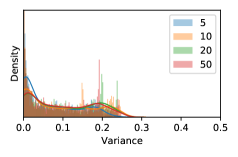

5.1 Distribution of Uncertainty Scores

Distribution of Uncertainty Scores Across Different Severity Levels As explained in Section 3, each uncertainty metric essentially defines an order/ranking among the data points. We conducted an analysis to better understand what data will be assigned high uncertainty under a particular uncertainty metric . Picking out the highest ranked data points (), we calculated the ratio of data points from each SL. Figure 4 summarizes the results as box plots for the Kaggle-DR and the Messidor-2 datasets; additional detailed statistics can be found in Table S.1 in the supplementary materials. From the plot and table, SL1 & SL2 examples account for a higher proportion among the top-ranked uncertain examples across the three ensemble methods. This finding matches our intuition that incipient disease examples (SL1 & SL2) are more likely to be considered uncertain by ensemble methods due to their ambiguity.

In contrast, the MC-dropout method showed the worst overall performance among the three, as it can be seen from the high ratios of SL0 examples among the uncertain negatives in Figure 4. The histograms in Figure 2 provides another perspective to look into the phenomenon, where a decent proportion of MC-dropout model’s predictions on SL0 inputs entailed low confidence (far from 0 or 1), which from another angle explained why MC-dropout was less specific in terms of lower FNP; many no-DR inputs (i.e. SL0) were erroneously assigned high uncertainty by MC-dropout models.

As discussed in Section 5.1 and Section 5.3 in the main paper, the mean metric and the stacking ensemble will have better performance in the precision (specificity) on the ambiguous data. Here, more detailed results are shown in Figures S.3 & S.6 and Table S.1. Figures S.3 & S.4 show the histograms of the uncertainty score for Kaggle-DR and Messidor-2 datasets that are the in-distribution (i.d.) dataset in our experiment and FigureS.5 & S.6 show the histograms for ImageNet and CIFAR-10 datasets, which is the o.o.d. datasets in our experiment. Each group of histograms contains results from the three evaluated ensemble methods (stacking ensemble, MC-dropout and TTA) and the three uncertainty metrics (mean, var and kl). Additional detailed results not displayed in Figure 4 can be found in Table S.1, which shows the proportion of the data of different SLs varies across different . For comparison, we also included in Table S.1 the results from single learners, and the proportions of data of different SLs (before any selection was made).